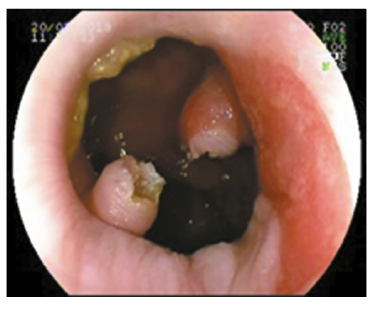

Se discutió con equipo de coloproctología las opciones respecto del abordaje terapéutico, considerando que no existía un beneficio significativo del proctológico sobre el endoscópico, y se optó en conjunto por la vía endoscópica. Se seccionó el puente mucoso con papilotomo de punta (Needle Knife, Boston, Scientifics, Natick, Massachusetts), se utilizó corriente de corte-coagulación con unidad electroquirúrgica ERBE ICC 200 (Efecto 3, 120-60 W), sin incidentes (Figuras 3 y 4).

En recto se observaron múltiples pseudopólipos.